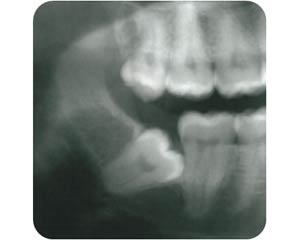

دندان نهفته